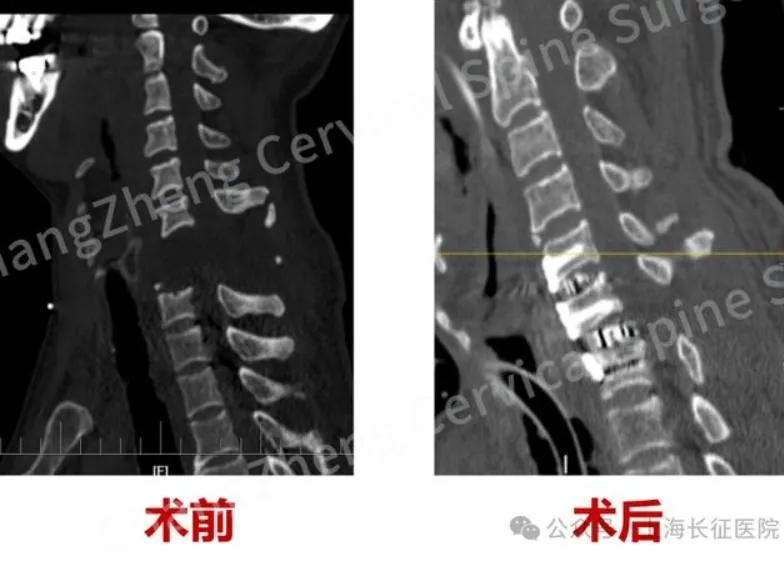

頸椎